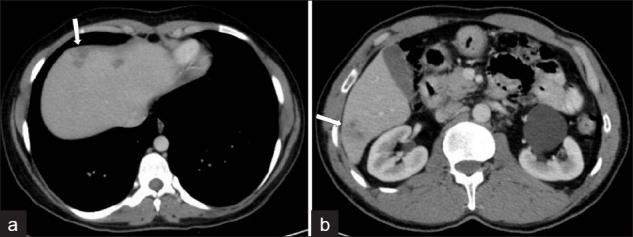

Fascioliasis refers to a zoonosis caused by Fasciola hepatica, a trematode infecting herbivores, but also occurs in humans who ingest the metacercaria found in fresh water plants. Infection in humans is common in developing countries and is also not uncommon in Europe. Diagnosis of this infection is difficult, as the history and symptoms are nonspecific and stool analysis for eggs is negative until the disease is in an advanced state by when the parasite has reached the biliary system. The clinical course consists of two phases; first a hepatic parenchymal phase in which immature larvae invade the liver parenchyma, followed by a ductal phase characterized by the excretion of larvae into the bile ducts. Parenchymal Phase: Ultrasonography (US) findings are nonspecific in this early phase. Computerized tomography (CT) may demonstrate subcapsular low attenuation regions in the liver. Magnetic Resonance imaging (MRI) can also be utilized to establish liver parenchymal involvement, and is better than CT in characterizing hemorrhagic lesions, as well as identifying more lesions relative to CT. Ductal Phase: US examination is most useful at this stage, with its ability to demonstrate the live movement of the worms within the dilated ducts. A CT demonstrates dilated central biliary ducts with periportal tracking, whereas, mild ductal dilatation is poorly appreciated under MRI. Therefore, familiarity with the multimodality imaging features of fascioliasis, in combination with an available confirmatory enzyme-linked immunoassay, would be most helpful for early diagnosis.

肝片吸虫病是一种由肝片吸虫引起的人畜共患病,这种吸虫感染食草动物,但人类摄入淡水植物中的囊蚴后也会感染。在发展中国家,人类感染这种疾病很常见,在欧洲也并不罕见。这种感染的诊断很困难,因为病史和症状不具有特异性,而且在疾病发展到晚期寄生虫进入胆道系统之前,粪便虫卵分析一直呈阴性。临床病程包括两个阶段:首先是肝实质期,未成熟幼虫侵入肝实质,随后是导管期,其特征是幼虫排入胆管。实质期:在此早期阶段,超声检查(US)结果不具有特异性。计算机断层扫描(CT)可能显示肝脏包膜下低密度区域。磁共振成像(MRI)也可用于确定肝实质受累情况,在表征出血性病变以及相对于CT识别更多病变方面比CT更好。导管期:US检查在这个阶段最有用,它能够显示扩张胆管内虫体的活动。CT显示中央胆管扩张并伴有门静脉周围条索状影,而在MRI下轻度胆管扩张不易被察觉。因此,熟悉肝片吸虫病的多模态影像学特征,并结合可用的确诊酶联免疫测定,对早期诊断最有帮助。